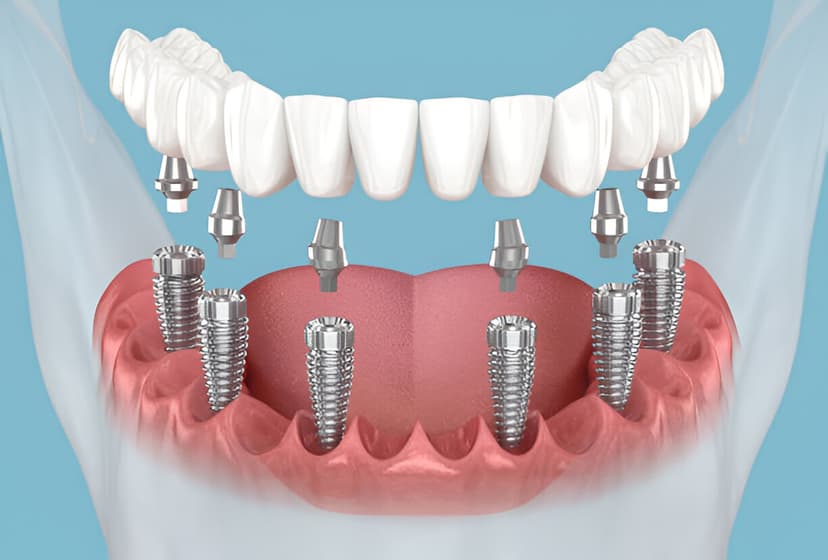

Implantes

Recupera la funcionalidad y estética de tus dientes con implantes dentales de titanio.

Nuestros implantes dentales cuentan con garantía de 4 años en el implante de titanio y 5 años en la corona. Utilizamos marcas reconocidas internacionalmente y seguimos protocolos estrictos de calidad.